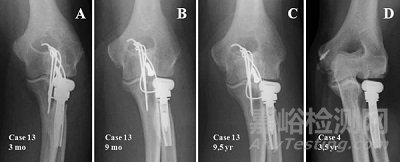

“過去,因?yàn)殛P(guān)節(jié)組件容易松動,所以在患有嚴(yán)重肩關(guān)節(jié)炎的年輕患者身上進(jìn)行關(guān)節(jié)置換手術(shù)是具有較高風(fēng)險的,早期關(guān)節(jié)置換手術(shù)失敗風(fēng)險較高,” IDE的主要研究者Hatzidakis博士說。“臨床試驗(yàn)表明,Stryker的Tornier Pyrocarbon肱骨頭非常令人滿意,我們追蹤最長的一位使用該設(shè)備的骨科患者已經(jīng)7年了。Tornier Pyrocarbon肱骨頭能夠顯著降低肩關(guān)節(jié)置換手術(shù)的風(fēng)險。為患者提供低風(fēng)險的肩關(guān)節(jié)置換植入物是史賽克一直以來的目標(biāo)。”